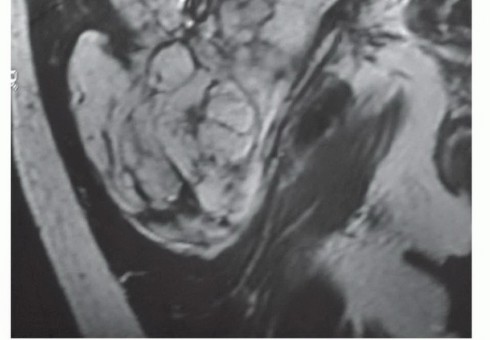

Magnetic Resonance Imaging (MRI) of the pelvis with and without intravenous contrast is the gold standard for local staging. T1-weighted images provide excellent anatomic detail regarding muscle involvement, fascial boundary integrity, and the displacement of the sciatic nerve. T2-weighted and STIR sequences are critical for highlighting peritumoral edema and the reactive zone, which must be encompassed within the surgical resection to avoid an intralesional margin. Contrast enhancement assists in differentiating viable tumor from a necrotic core. Computed Tomography (CT) of the chest is mandatory for systemic staging to rule out pulmonary metastasis, the most common site of dissemination for soft tissue sarcomas.

Clinical & Radiographic Imaging